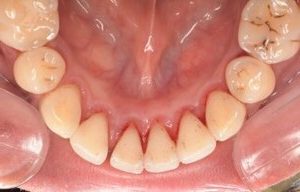

CASE 3

Before

After

基本情報

| 年齢・性別 | 30代・女性 |

|---|---|

| 主訴 | 定期検診 |

| 治療内容 | PMTC |

| 治療期間 | 60分 |

| 治療費 | 5,750円 |

| リスク・副作用 | しみる可能性があります。 |

| 治療方針 | PMTCでステインの除去。 |

| 担当者所見 | ステインが付きやすいため、3カ月毎の定期検診で除去する。 |